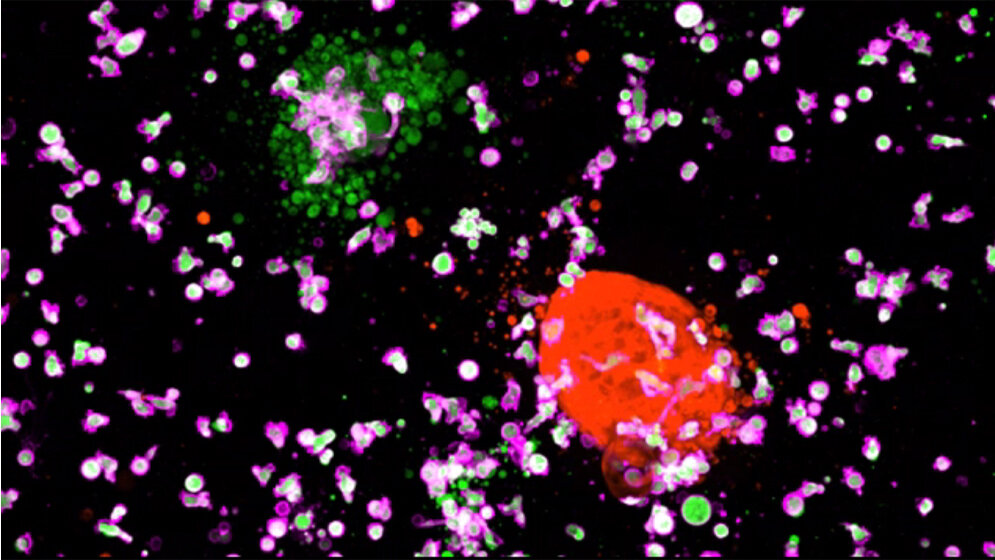

In der aktuellen Studie stellten er und seine Kollegen dreidimensionale Tumorkulturen aus Gewebeproben von Dickdarmkrebspatienten her. Mit diesen Tumor-Organoiden und Organoiden aus gesunden Darmzellen testeten sie, wie effektiv unterschiedliche CAR-NK-Zelllinien Darmkrebszellen zerstören und welche Schäden sie möglicherweise auch bei gesunden Zellen anrichten. Die Mini-Tumoren wurden von den Wissenschaftlern gentechnisch so verändert, dass die Krebszellen messbare Lichtsignale aussenden. Je mehr Krebszellen durch die Killerzellen abgetötet wurden, desto schwächer wurde das Lichtsignal. Mit dieser Methode konnten die Wissenschaftler live unter dem Mikroskop verfolgen, wie effektiv und wie spezifisch die Abwehrzellen die Krebszellen eliminierten.

Richteten die Forscher die Killerzellen gegen ein Oberflächenprotein, das sowohl in entarteten wie auch in gesunden Zellen vorkommt, wurden Tumor- und normale Organoide gleichermaßen angegriffen. Abwehrzellen, die gegen ein krebsspezifisches Rezeptorprotein gerichtet waren, zerstörten dagegen nur die Krebszellen und griffen keine gesunden Zellen an (Video). Auf diese Weise entdeckten die Wissenschaftler auch, dass der bekannte Signalrezeptor FRIZZLED für die CAR-NK-Zell-Therapie ein weniger geeignetes Angriffsziel ist, als ursprünglich angenommen. FRIZZLED wird in bestimmten Darmkrebstumoren in besonders großen Mengen produziert. Die Anti-FRIZZLED-Killerzellen schädigten jedoch auch die gesunden Organoide, eine wichtige Erkenntnis für die Entwicklung von Therapien mit FRIZZLED als Angriffsziel.